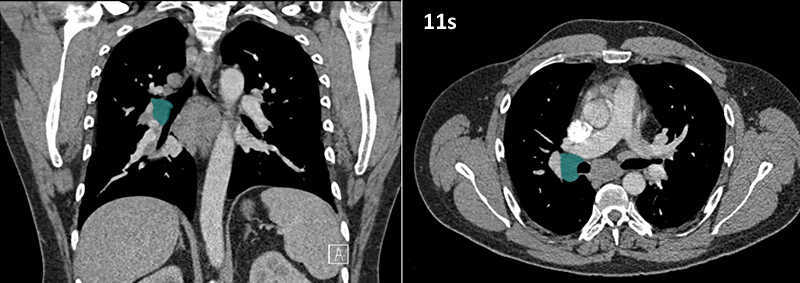

Nodal zones and stations according to the International Association for the Study of Lung Cancer (IASLC) node map.

Table (above): Nodal zones and stations according to the International Association for the Study of Lung Cancer (IASLC) node map. (Source: 1,2) *Depends on the side of the tumour.